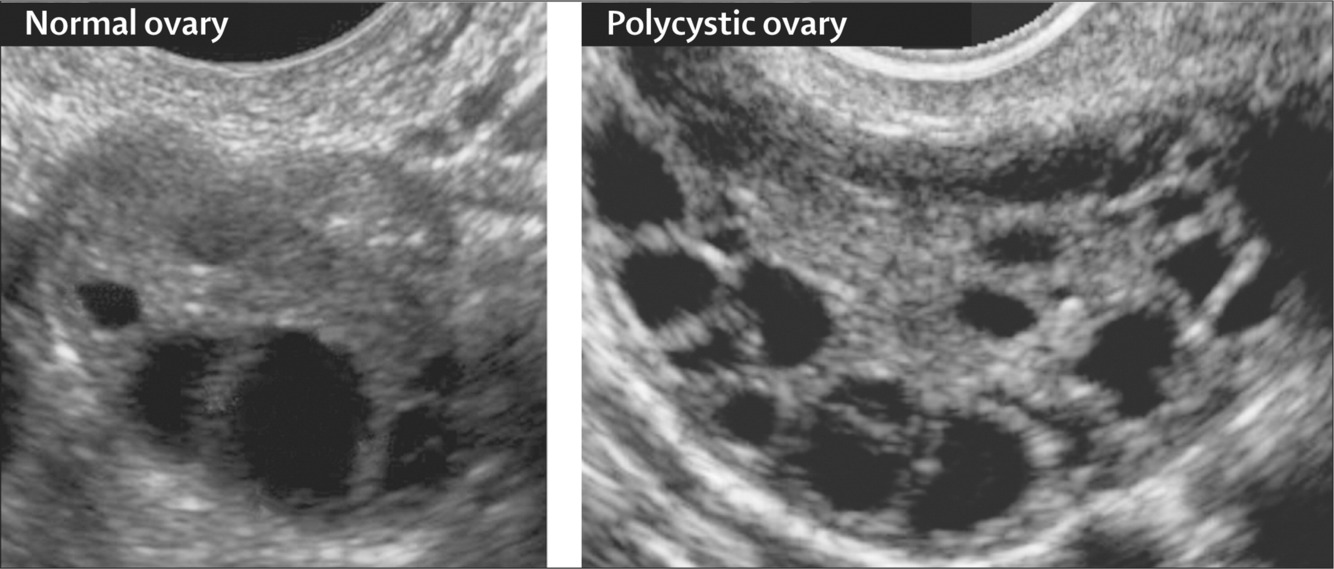

3. polycystic ovaries on ultrasound

1. 12 or more in 1 or both ovaries (string of pearls)

2. ovarian volume over >10cm3

pelvic ultrasound scan

transvaginal ultrasound is gold standard for visualising the ovaries - string of pearls as follicles arranged around the periphery of the ovary or ovarian volume of 10cm3 or more

not reliable in adolescents at diagnosing PCOS